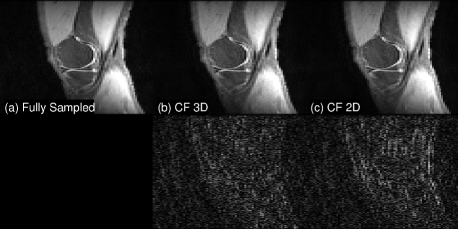

For 3D, we truncated a 3T knee dataset (downloaded from mridata.org) to , then retrospectively downsampled in and using 2D random sampling, with ACS and fully sampled . The data were compressed to four virtual coils for faster processing. A representative slice is shown in Figure 2. Since 3D CF reconstruction utilizes similarity and redundancy in three dimensions, with smaller degrees of freedom, it is able to outperform 2D CF reconstruction, which was separately applied to individual 2D slices. Due to prohibitive memory requirements, it was not feasible to extend SAKE’s implementation to 3D.